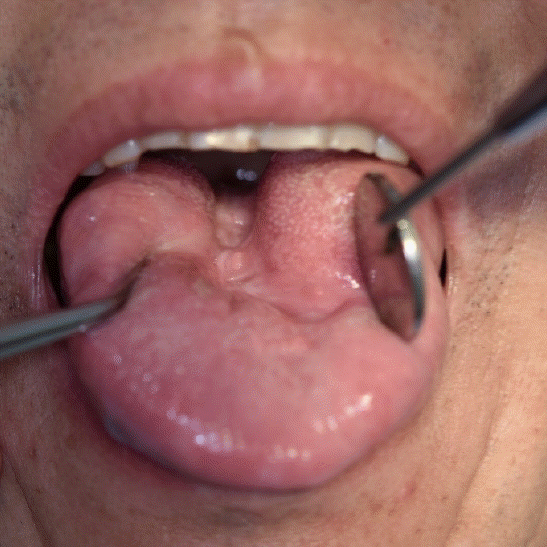

A 55-year-old man with a history of dyslipidemia and fatty liver presented to Kyungpook National University Hospital emergency center on May 10, 2023, with complaints of abdominal pain and vomiting that began the day prior. The patient reported significant alcohol consumption, including two bottles of alcohol daily for the past month and at least one bottle per meal over the previous 10 days. Initial laboratory evaluations revealed stage 3 acute kidney injury and severe metabolic acidosis, prompting the initiation of continuous renal replacement therapy (CRRT). Upon arrival, he was alert but exhibited hypotension (105/48 mmHg) and hypoxemia (SpO₂ 80%). Fluid resuscitation (125 cc/hr) and supplemental oxygen (15 L/min) were administered. However, within two hours, his condition rapidly deteriorated, with a decline in mental status to a semi-comatose state, blood pressure dropping to 59/27 mmHg, and oxygen saturation further decreasing to 71%. The patient was subsequently admitted to the intensive care unit (ICU), requiring continuous vasopressor support and mechanical ventilation via endotracheal intubation. Norepinephrine (Norpin 0.1% 10ml) mixed with dextrose infusion was initiated at 10 cc/hr but showed no significant improvement, necessitating an increase to 20 cc/hr. Vasopressin 20u/1ml was mixed with Normal saline and infusion was initiated at 5cc/hr. Epinephrine mixed with Normal saline was concurrently administered at 10 cc/hr. Vasopressor support continued for six days post-admission. On the second day of admission, tenderness and skin discoloration developed in the limbS region, followed by bullae formation and extensive skin detachment by May 12 (Fig. 1). Laboratory findings indicated disseminated intravascular coagulation (DIC), with markedly elevated d-dimer levels (>20), severe thrombocytopenia (platelet count 15 × 10⁹/L), hypofibrinogenemia (78 mg/dL), prolonged prothrombin time (23 seconds), activated partial thromboplastin time (53.8 seconds), and reduced antithrombin III (35.1%). Abdominal computed tomography (CT) revealed a hypoattenuated liver lesion, suggesting multiple organ failure. Antithrombin III injections were administered as part of DIC management. On the 9th day of admission, as the patient’s vital signs improved, he was transferred from the ICU to a general ward. However, progressive skin detachment continued, and dry gangrene of the right second finger was noted (Fig. 2). Vascular surgery consultation confirmed inotrope-induced necrosis. On the following day, endotracheal intubation was removed. Oral examination post-extubation revealed widespread mucosal discoloration and blood clots affecting the palate, gingiva, and tongue (Fig. 3). On the 14th day of admission, the department of oral and maxillofacial surgery was consulted for oral care. With no active bleeding, conservative management using chlorhexidine dressings was initiated. While mucosal discoloration of the palate and gingiva improved, tongue discoloration worsened progressively. On June 4, necrosis of the tongue was confirmed, leading to re-evaluation by the oral and maxillofacial surgery team. Passive debridement and hydrogen peroxide dressings were performed (Fig. 4). The patient was discharged on June 20 and returned for outpatient follow-up two days later. Residual necrotic tissue was removed, and at the two-week postoperative follow-up, healing was favorable with no recurrence. At a follow-up evaluation 1 year and 4 months later, no additional complications were observed (Fig. 5).